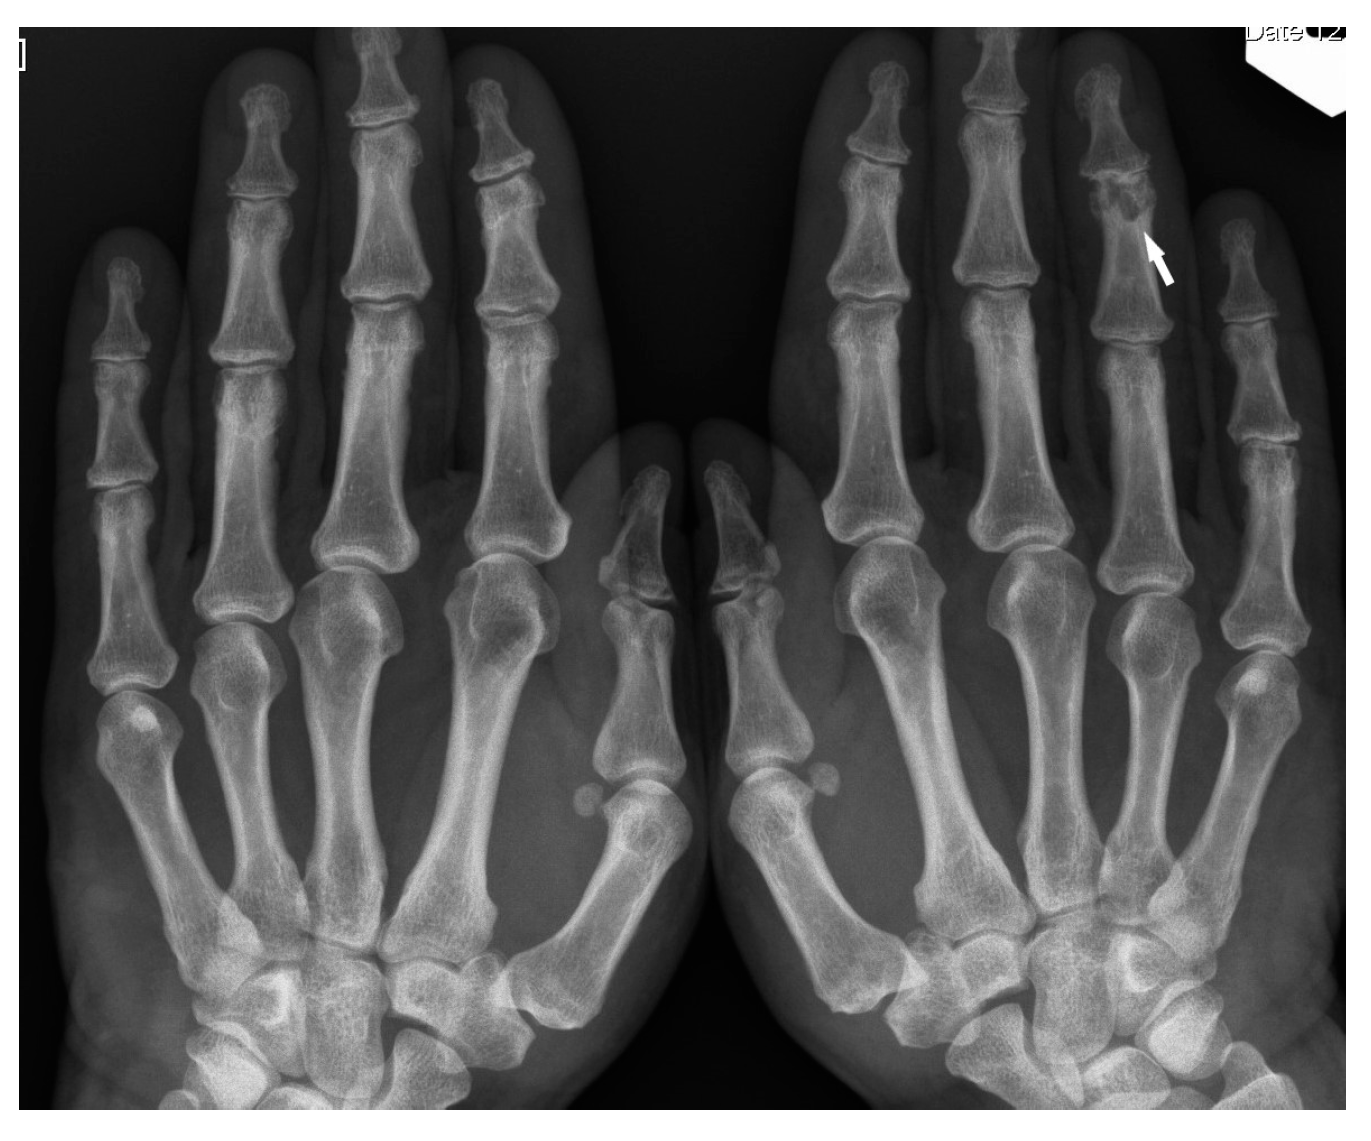

Bone sarcoidosis was first described in 1903 by Kreibich as the image of lace in the phalanges of the hands and this is considered the classic presentation of small bone involvement [8].

The typical cystic X-ray pattern of bone sarcoidosis was described for small bones of the hands only (Figure 1). Other skeletal sites of sarcoidosis evaluated by this modality may be a diagnostic challenge, showing no typical radiologic features of the disease. Increasingly used modern diagnostic methods such as MRI and PET-CT indicate that multifocal bone lesions are sometimes undetectable on X-ray [10,11,12].

Only the radiological pattern of the lesions in the phalanges of the hands and feet, resembling a lace on X-ray, is described as characteristic of bone sarcoidosis.

The radiographic appearance of phalanges occupied by sarcoidosis includes lytic lesions of various sizes, called cysts. Cystic lesions, mostly punched-out, may be accompanied by soft tissue nodules. The presence of large cysts increase the risk of pathological bone fracture [20] (Figure 6a,b). Numerous small cysts are more frequently observed. The articular surfaces are preserved, although cysts located in the subchondral layer might mimic erosions (Figure 7). Periosteitis is uncommon.

Figure 1. X-ray of the finger. Sarcoidosis. Cystic lesions in the middle phalanx head (white arrow).

Figure 7. X-ray of the hands, PA. Unilateral osteolytic-cystic lesions in the subchondral layer of the middle phalanx of the 4th finger of the left hand (white arrow).